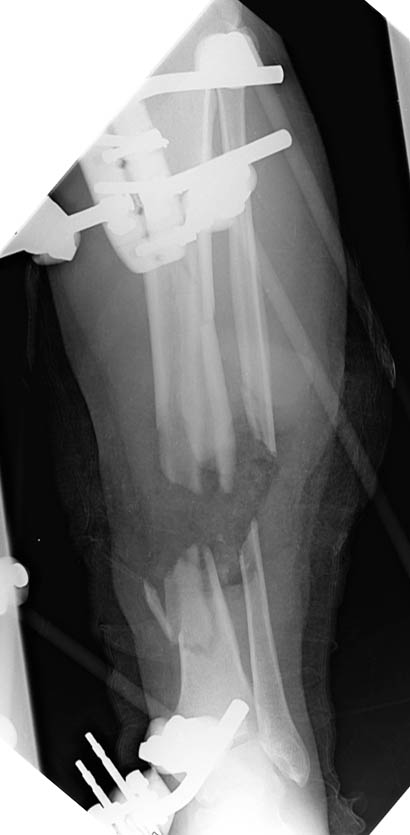

Attached are the pre and post debridement radiographs of the L leg of a 47 y.o rancher flown in (to Univ of Utah) from Wyoming. Very close range, high velocity round to leg (.22-250, which the ranchers use mostly to shoot coyotes). Dips Copenhagen, no other medical issues. 6'2", 225 lbs. Spends most of his day on and off horses and working the ranch.

Plantar sensation present. No dorsal sensation. 2+ palp pt,doppler signal in dp is retrograde flow. Anterior compartment, lateral compartment, and half of deep posterior compartment gone. Clinical photos not available at this time (photocard reader won't work right now).

Defect is Lat Dorsi sized, with very healthy appearing stump of A-Tib available. Bony defect (when measured vs. contralateral radiographs) is between 6 and 7 cm.

With regards to the degree of bony debridement , I think the presentation film was deceiving. The limb was foreshortened in the field splint, and I believe that any "large" pieces of tibia are in a Wyoming pasture. His length as set in the frame was based on the contralateral limb.

I am not really comfortable with transport over a nail given that coronal split that runs right up into the metaphysis.